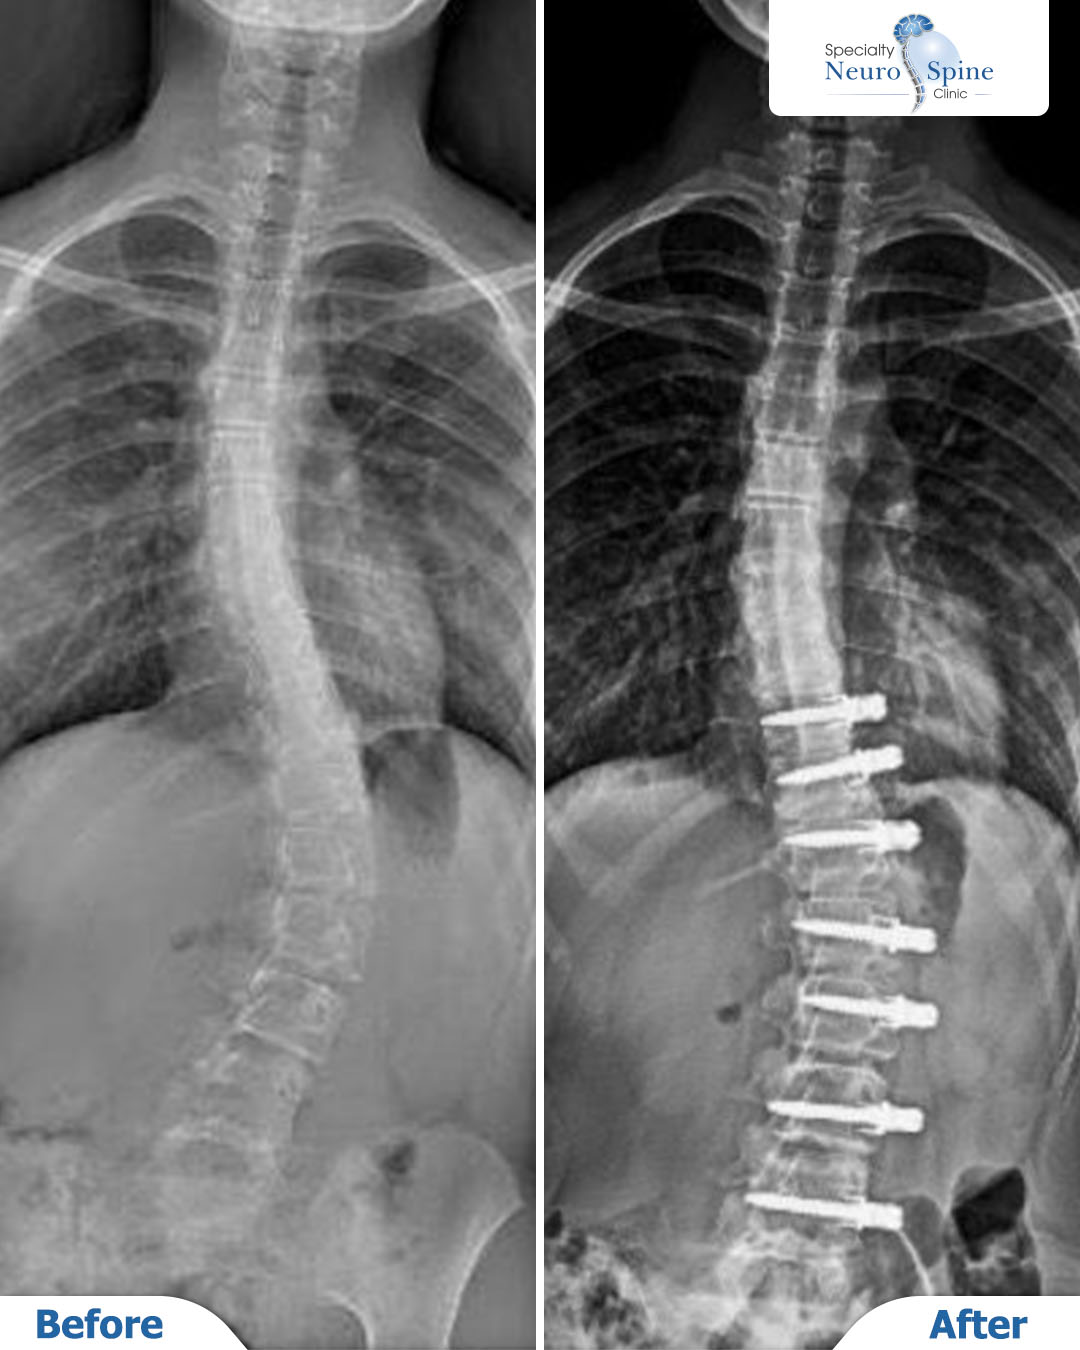

Our hero patient Lilyan, 12 years old from Jordan, was diagnosed with spinal curvature at an early age

After carefully studying her case, a curvature correction surgery was performed for her using the Vertebral Body Tethering (VBT) technique, which is a modern technique aiming to preserve natural spinal growth, flexibility, and continued growth.

X-ray images of our young hero, Lillian (12 years old from Jordan), demonstrate the significant correction in spinal alignment following the procedure, which addressed the curvature extending from the 10th thoracic vertebra (T10) to the 4th lumbar vertebra (L4).

This surgical intervention successfully restored spinal balance at an early age—a critical factor in ensuring healthy and stable development without hindering the natural growth process.

The procedure was performed using the advanced Vertebral Body Tethering (VBT) technique. This cutting-edge technology corrects the curvature while preserving the spine’s natural growth and flexibility, allowing for continued, balanced development without the need for full spinal fusion.